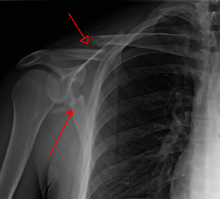

A scapular fracture is a fracture of the scapula, the shoulder blade. The scapula is sturdy and located in a protected place, so it rarely breaks. When it does, it is an indication that the individual was subjected to a considerable amount of force and that severe chest trauma may be present.[1] High-speed vehicle accidents are the most common cause. This could be anywhere from a car accident, motorcycle crash, or high speed bicycle crash but falls and blows to the area can also be responsible for the injury. Signs and symptoms are similar to those of other fractures: they include pain, tenderness, and reduced motion of the affected area although symptoms can take a couple of days to appear. Imaging techniques such as X-ray are used to diagnose scapular fracture, but the injury may not be noticed in part because it is so frequently accompanied by other, severe injuries that demand attention. The injuries that usually accompany scapular fracture generally have the greatest impact on the patient's outcome. However, the injury can also occur by itself; when it does, it does not present a significant threat to life. Treatment involves pain control and immobilizing the affected area, and, later, physical therapy.

Most fractures of the scapula can be seen on a chest X-ray; however, they may be missed during examination of the film.[1] Serious associated injuries may distract from the scapular injury,[4] and diagnosis is often delayed.[3] Computed tomography may also be used.[1] Scapular fractures can be detected in the standard chest and shoulder radiographs that are given to patients who have suffered significant physical trauma, but much of the scapula is hidden by the ribs on standard chest X-rays.[4] Therefore, if scapular injury is suspected, more specific images of the scapular area can be taken.[4]